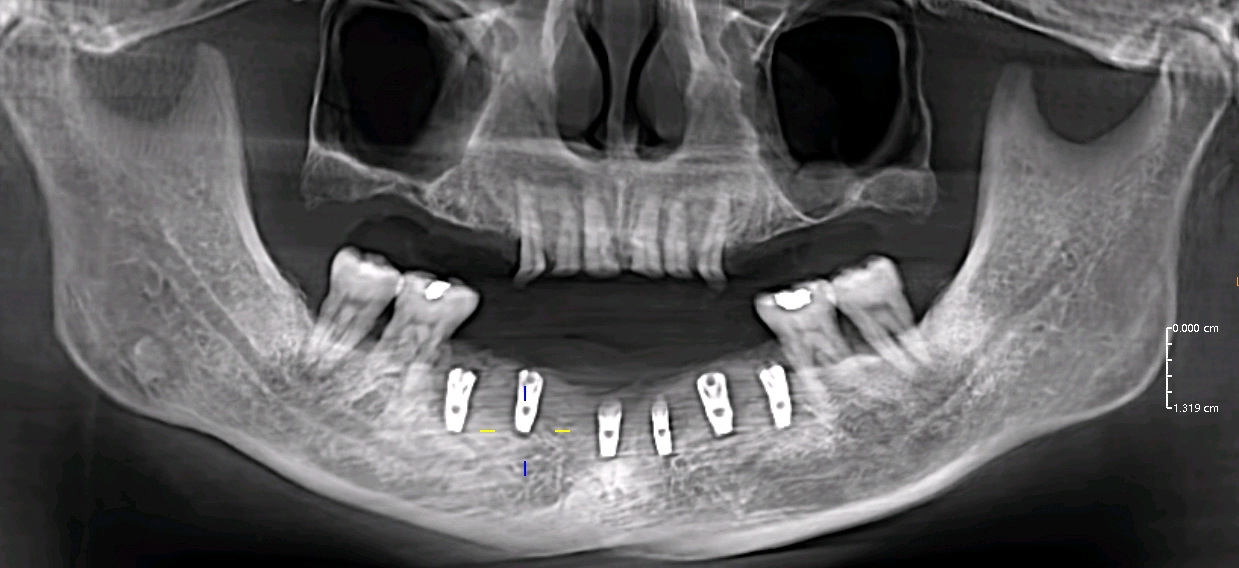

- X-rays to monitor jawbone density and implant stability.